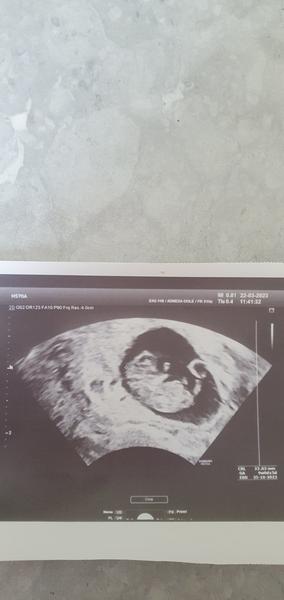

No všímam si co čítam ze sme tu skoro všetky v rovnakom týždni ja som tiež 9tt zajtra potvrdi presne koľko to je takze asi sme boli všetky tak nejako spoločne 🥰